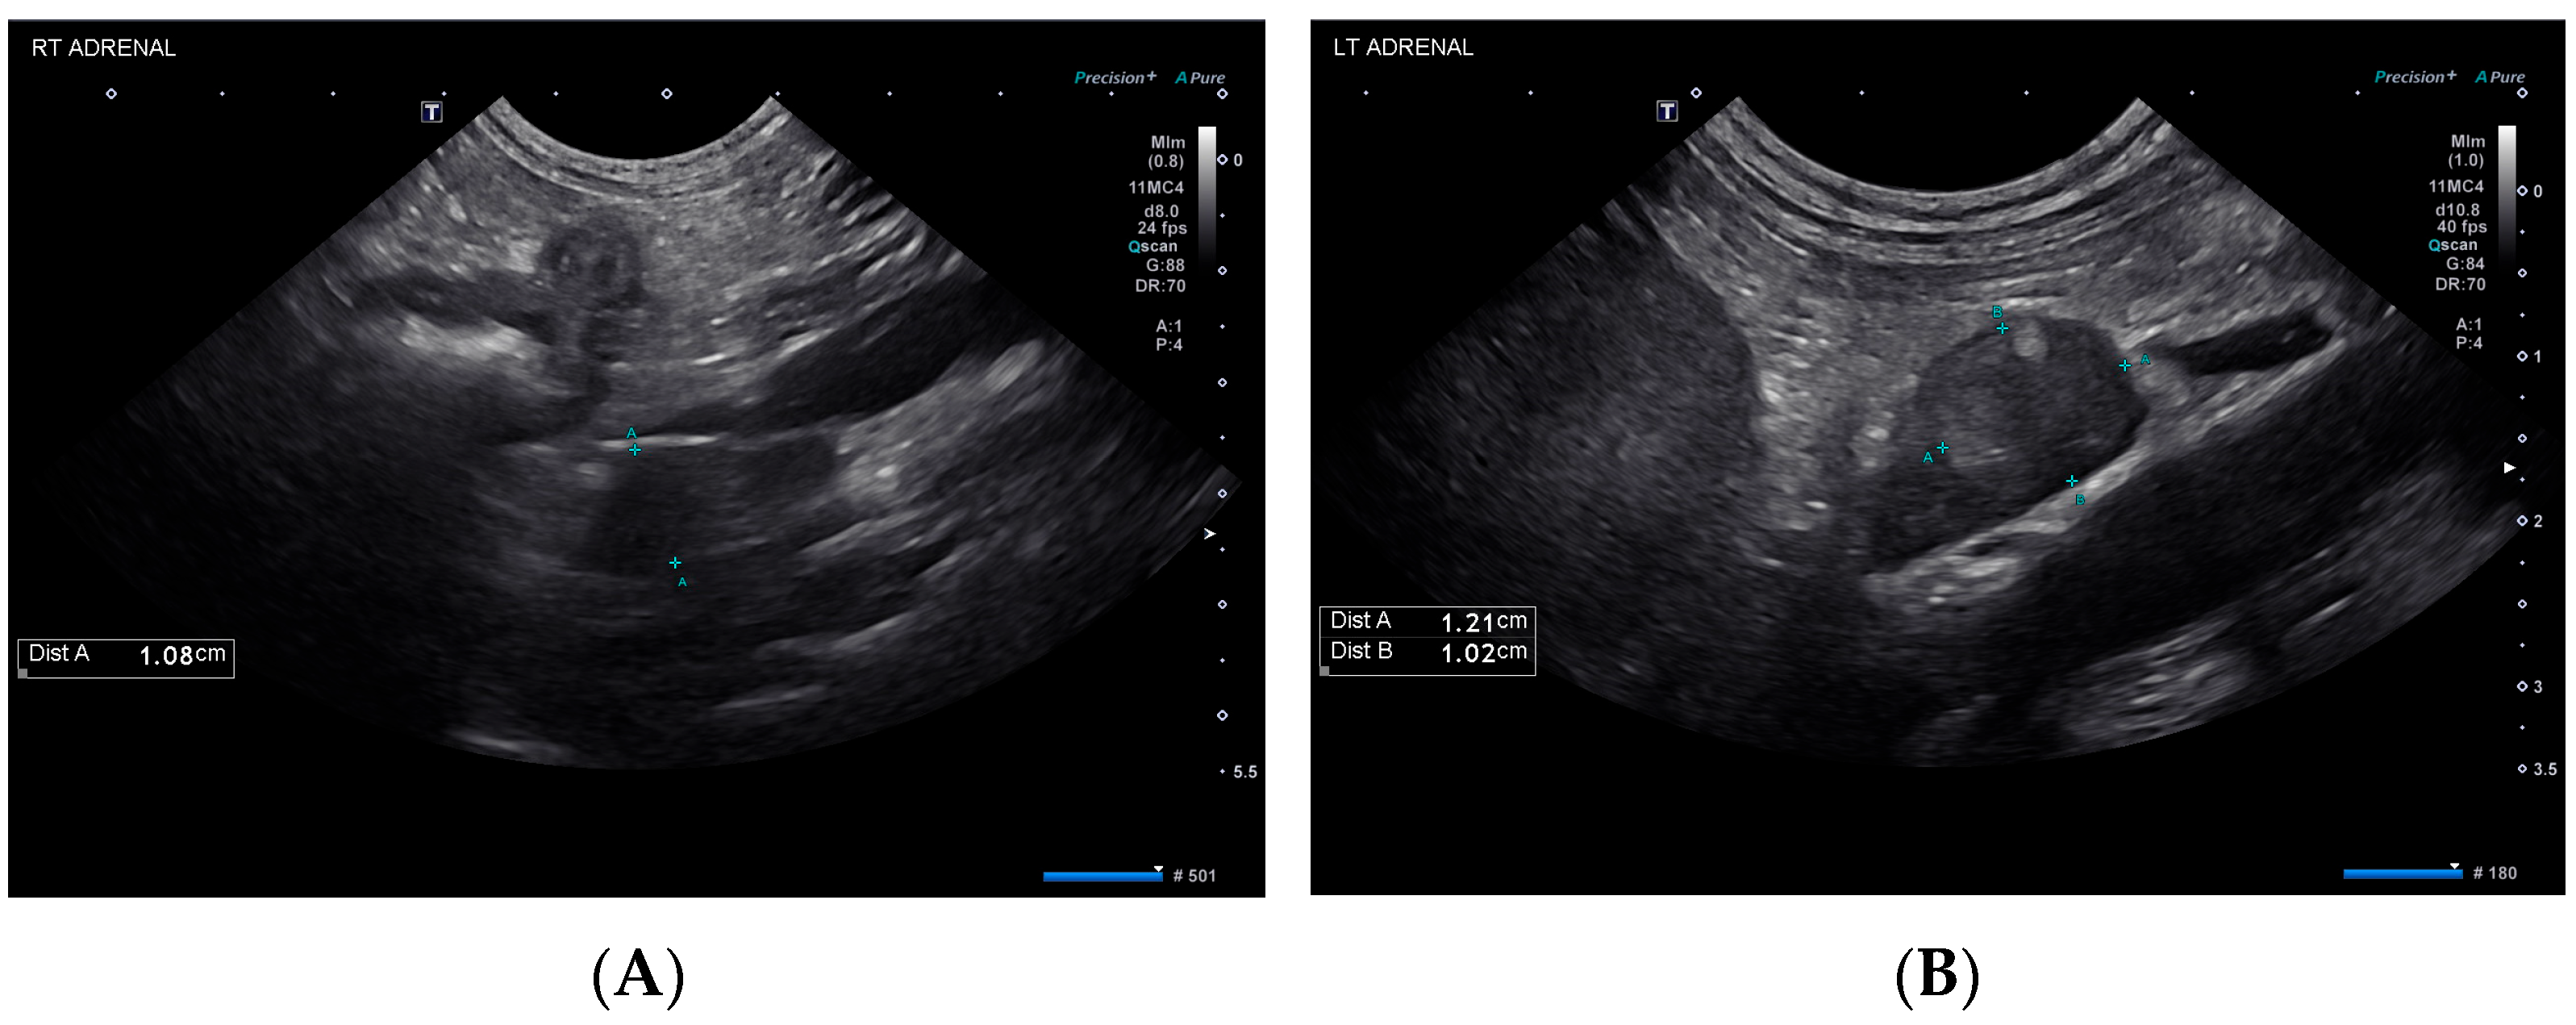

The following day (day 25), the patient was observed to be dull and weak. She was hypoglycemic (69 mg/dL), so a 50% dextrose bolus was administered, and a dextrose continuous rate infusion was initiated. Subsequent recheck blood glucose values were normal. Abdominal ultrasound showed mild submucosal and muscularis thickening of the small bowel with preserved mural architecture and bilateral adrenal nodules (Figure 2), similar in appearance compared to prior. The liver was progressively and diffusely hypoechoic with rounded margins while the cholecystic changes had resolved.

Figure 2.

Ultrasonographic findings of the right (A) and left (B) adrenal glands on day 25.

The dog in this case report was diagnosed with amanitin intoxication and subsequent hepatic dysfunction based on the detection of a trace concentration of alpha-amanitin in urine. She recovered and was diagnosed with typical hypoadrenocorticism (HA) 25 days post-initial presentation. The chronology of these events suggests that alpha-amanitin intoxication might have resulted in an adrenocortical injury leading to HA. Given the normal plasma aldosterone concentration on day 1, the patient likely did not have aldosterone deficiency at this time, but this result does not rule out pre-existing cortisol deficiency. Hypoadrenocorticism could have developed in this dog independent of the intoxication caused by idiopathic destruction, immune-mediated or metastatic disease or an ischemic event [11,12,13]. However, the dog’s initial and subsequent diagnostic work-up revealed no evidence of embolic disease or neoplasia, making these differentials unlikely. The initial ultrasound evaluation of the dog revealed mild bilateral adenomegaly, with measurements greater than typically reported for dogs with HA [14,15]. This finding could represent active adrenalitis or may be an incidental finding as the adrenal glands appeared and measured similarly at recheck ultrasound examination on day 25. Without histopathological evaluation of this dog’s adrenal glands, the definitive cause for the development of HA remains a conjecture, but amanitin intoxication is a top differential.